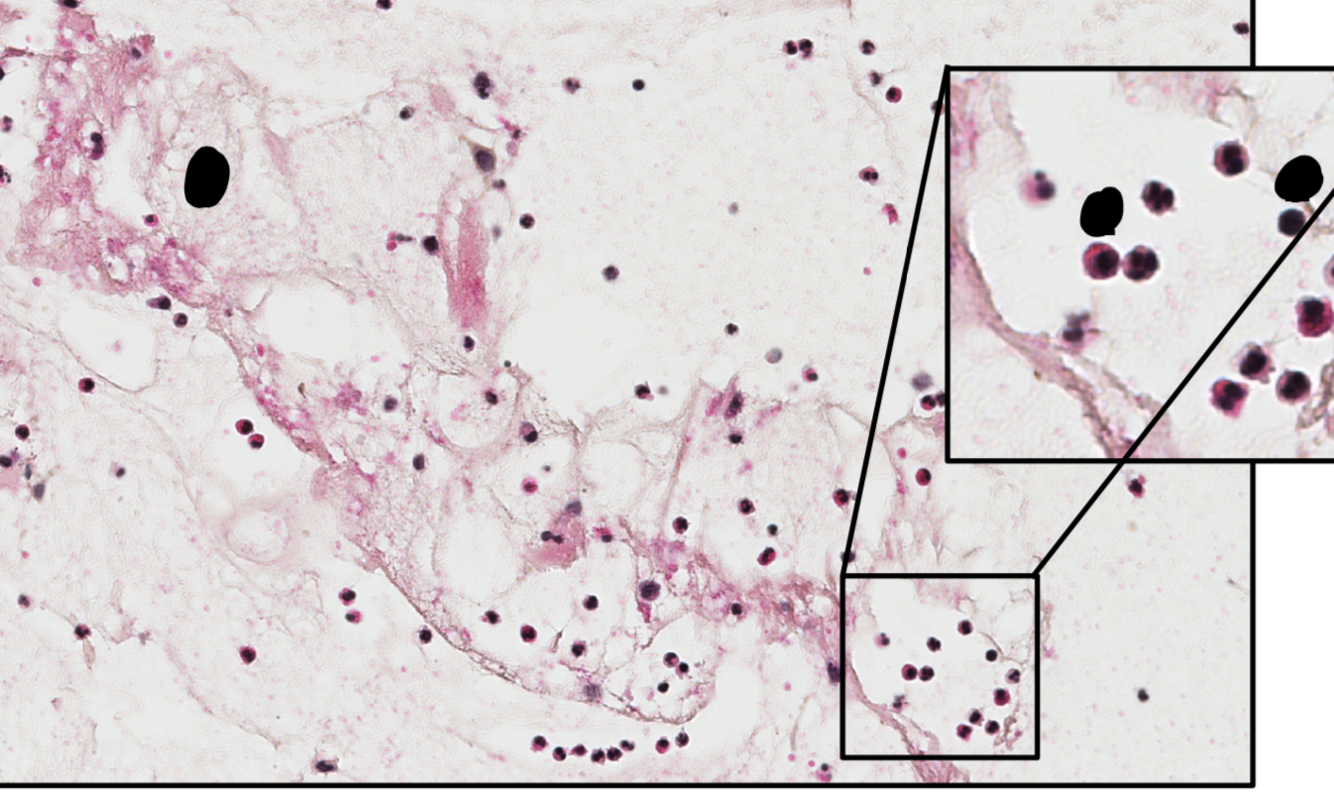

hémosidérose rénale